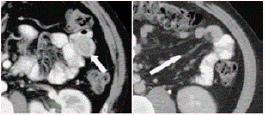

Diffuse wall edema of the transverse ascending colon and splenic angle, image of invaginated appearance and space-occupying lesion at this level can be observed in abdomen and pelvis tomography (Figures 3 and 4).

Crescent in doughnut sign. Imaging of oral phase showing enteroenteric intussusception. The arrow points the external muscularis of intussusception.

Figure 3: Crescent in doughnut sign. Imaging of oral phase showing enteroenteric intussusception. The arrow points the external muscularis of intussusception.

Source: Document obtained during the study.

Pathognomonic findings in tomography include bowel thinning, space-occupying lesion and an area of fat and vessel hyperdensity. The computed tomography (CT) performed on the reported patient showed diffuse edema of the transverse ascending colon wall and splenic angle, image of invaginated aspect and space-occupying lesion. 24 Nuclear Magnetic Resonance Morphology is similar to CT and consistent with other studies. 25